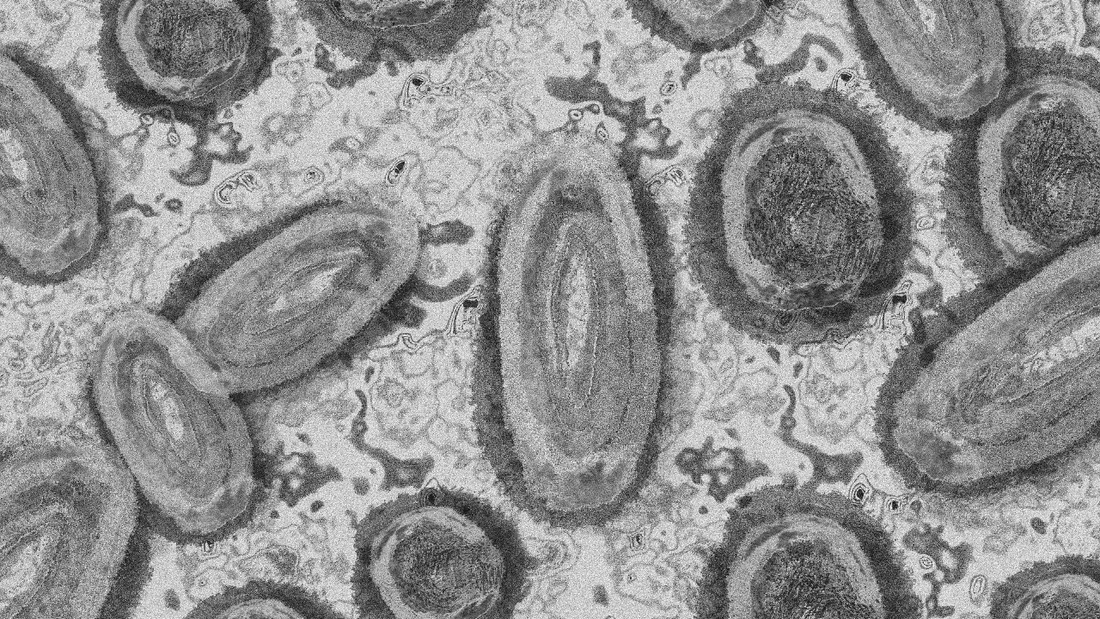

Variole du singe : l'OMS lance son alerte la plus élevée et met en garde contre toute stigmatisation

Décelée pour la première fois chez l'humain en 1970, la variole du singe est moins dangereuse et contagieuse que sa cousine la variole humaine, éradiquée en 1980.